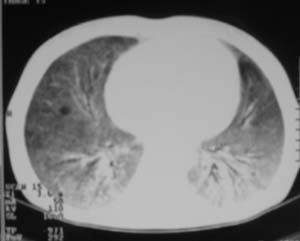

以下是引用zjzjr在2007-9-20 12:29:00的发言:[br]双肺磨玻璃改变,考虑肺水肿.

以下是引用yangzongshan在2007-9-20 18:29:00的发言:[br]两肺毛玻璃样改变,其内可见肺纹理影,无胸腔积液,故考虑肺泡蛋白沉积症

以下是引用276894491在2007-9-20 13:40:00的发言:[br]考虑肺水肿;外源性过敏性肺炎不排除。

以下是引用逸风在2007-9-20 20:45:00的发言:[br]两肺磨玻璃样改变,临床病史短,发热,考虑病毒感染合并右肺代偿性肺气肿.待排肺水肿,病史短,不支持肺泡蛋白沉着症.